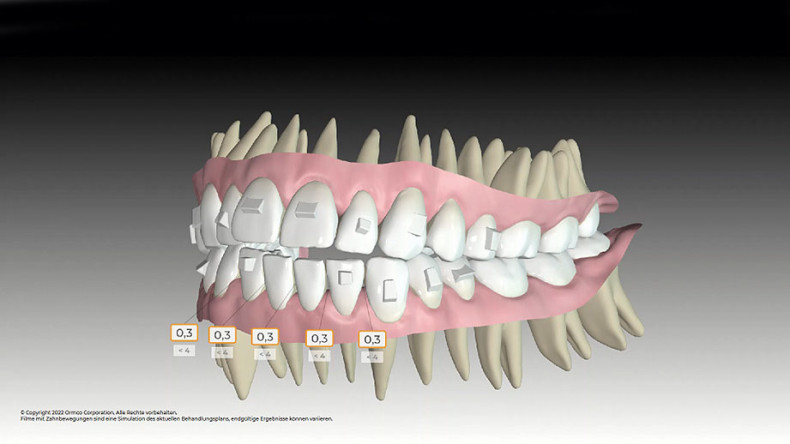

Die Patientin wurde über die möglichen Therapieoptionen der kombiniert kieferorthopädisch-kieferchirurgischen oder rein festsitzenden Therapie aufgeklärt, welche sie jedoch ablehnte. Ebenso lehnte die Patientin die Extraktion von vier Prämolaren ab. Somit fiel die Wahl auf die Behandlungsoption mit Alignern (SPARKTM System, Fa. Ormco). Nachdem die Patientin logopädisch behandelt und das viszerale Schluckmuster umgestellt worden war, konnte mit der Planung des Falls begonnen werden. Aufgrund der abgelehnten Therapieoptionen entfiel die Möglichkeit der Seitenzahnintrusion und man konzentrierte sich auf die Frontzahnextrusion als primäres Behandlungsziel.

Dazu wurde die Approver 3D© Software eingesetzt, welche neben der Kronenbewegung auch die Bewegung der Wurzeln simulieren kann. Es wurden 20 Schienen und eine approximale Schmelzreduktion (ASR) an den unteren Frontzähnen zwischen 33 und 43 von je 0,3 mm geplant.

Durch sogenannte Optimized-Extrusion-Attachments wurde eine Extrusion der oberen Frontzähne von max. 2,3 mm und der unteren Frontzähne von max. 1,4 mm geplant (Abb. 4a–c). Mithilfe einer leichten Expansion der Prämolarenregion konnte der Platzmangel im Oberkiefer ohne ASR kompensiert werden.